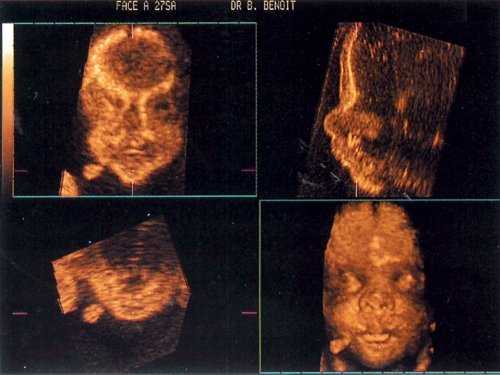

- поверхностный метод, который позволяет получить фотореалистичные изображения (рис. 2);

- 3D. Отличается от двухмерного изображения тем, что прибавляется ещё один параметр — глубина. На экране монитора появляется трёхмерная картинка. Если на исследование пришла будущая мама, она сможет увидеть личико своего малыша, а также рассмотреть строение его тельца. Пол будущего ребёнка на трёхмерном аппарате устанавливается с точностью 100%. По длительности процедура 3Д УЗИ занимает около 50 минут.